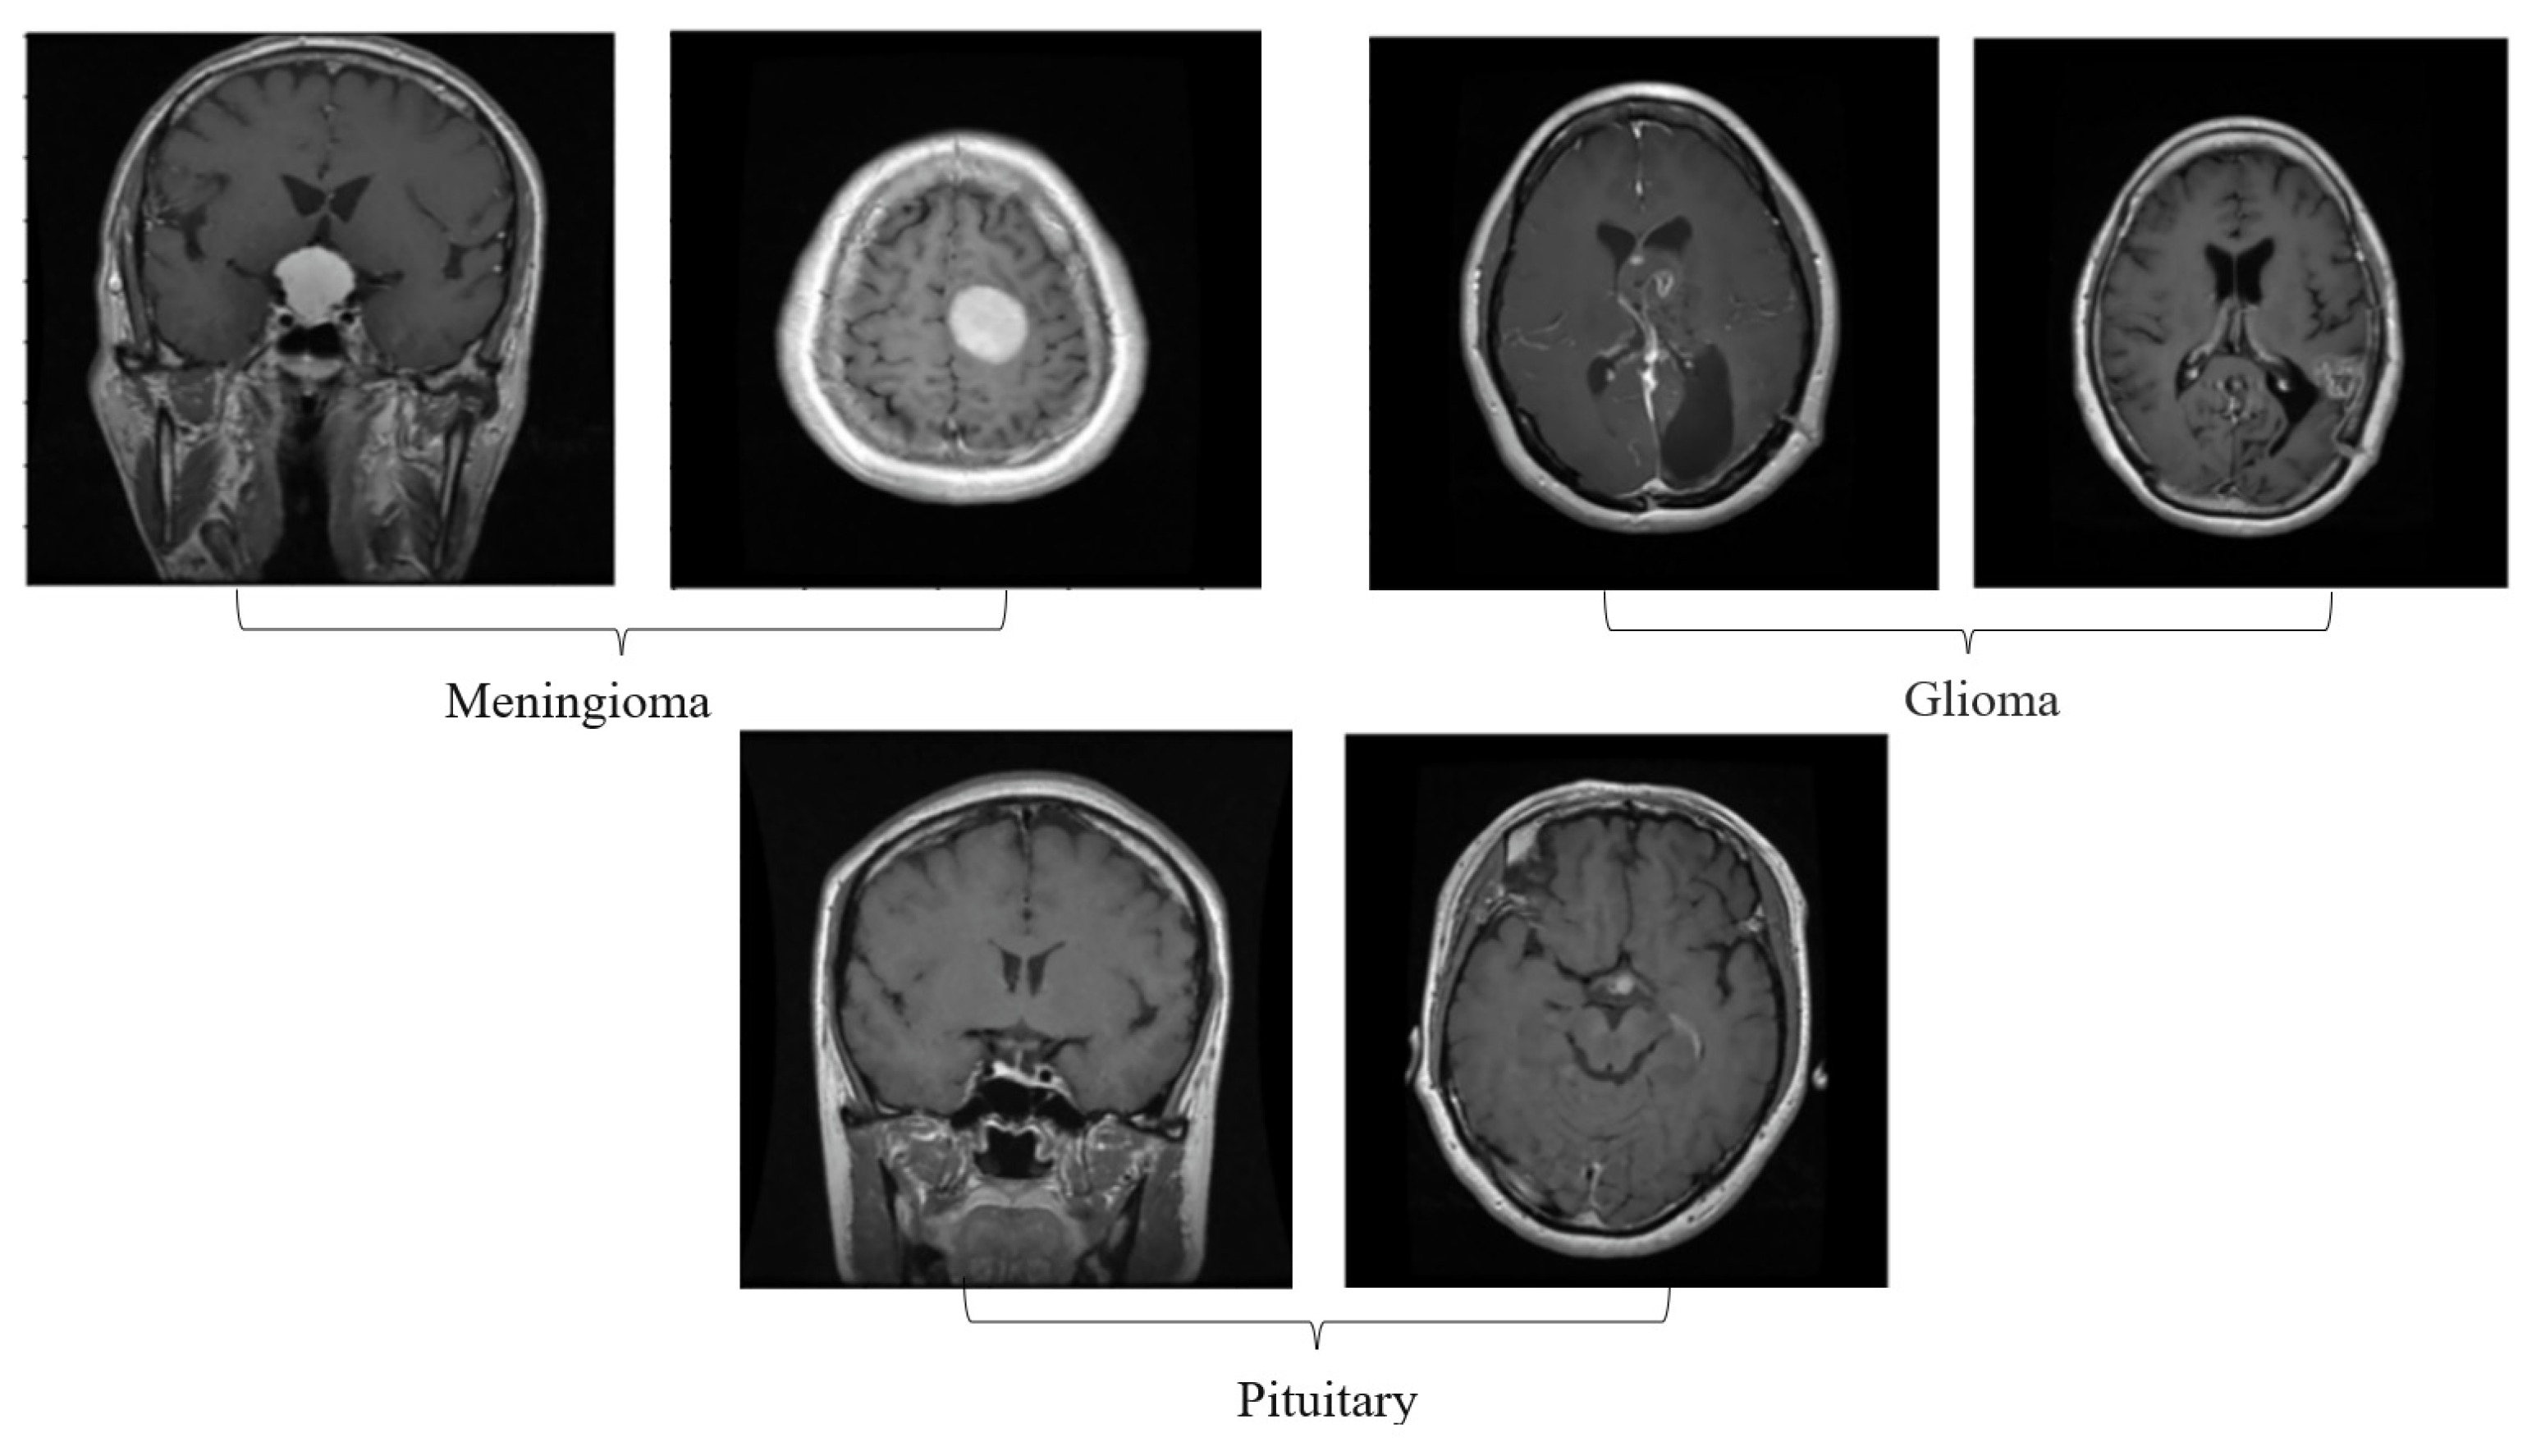

3. Proposed System